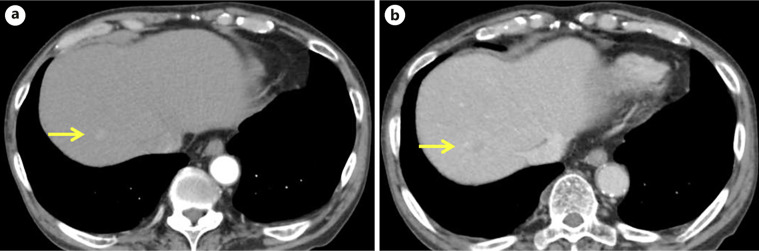

Case presentation: A 74-year-old man was admitted for the evaluation of liver tumors. His medical history included a chronic, intractable idiopathic right forearm AVF, for which he had undergone multiple surgical interventions. Abdominal EOB-MRI revealed multiple small focal lesions across both liver lobes during the hepatobiliary phase, indicative of multiple HCC, and liver biopsy confirmed early-stage HCC. Considering the potential presence of additional vascular anomalies similar to the forearm AVF, local hepatic artery chemoembolization was performed. Since there is still insufficient discussion about the systemic administration of angiogenesis inhibitors to patients with vascular abnormalities such as AVF, we discuss the treatment options for HCC with AVF, including its strategies in the progressed HCC stage.